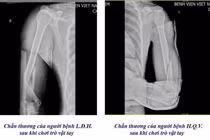

Trung tâm Y tế khu vực Đoan Hùng vừa tiếp nhận trường hợp bệnh nhi C.N.G.H, 13 tuổi, trú tại xã Tây Cốc, được gia đình đưa vào viện trong tình trạng đau nhiều vùng cẳng tay trái, hạn chế vận động sau khi ngã chống tay xuống đất khi chơi đá bóng.

Qua thăm khám lâm sàng kết hợp chẩn đoán hình ảnh, các bác sĩ xác định bệnh nhi gãy kín 1/3 dưới hai xương cẳng tay trái - một dạng chấn thương thường gặp ở lứa tuổi thiếu niên do xương đang trong giai đoạn phát triển, mật độ xương chưa hoàn toàn hoàn thiện.

Tại khoa Ngoại tổng hợp và Liên chuyên khoa, các bác sĩ đã tiến hành gây mê, kéo nắn chỉnh lại trục xương và bó bột cố định nhằm đảm bảo phục hồi đúng giải phẫu, ngăn ngừa biến chứng lệch trục hoặc hạn chế vận động sau này. Hiện tại bệnh nhi đã điều trị ổn định và ra viện, bác sĩ đã hẹn lịch tái khám trong vài ngày tới.

Bệnh nhi 13 tuổi gãy hai xương cẳng tay khi đá bóng - Ảnh BVCC